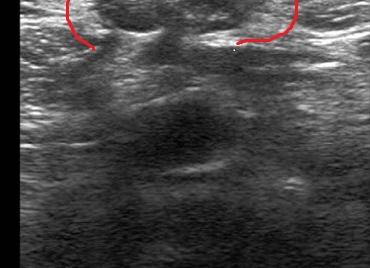

УЗИ грыжи

УЗИ при грыже, что показывает?

Результаты ультразвукового исследования передней брюшной стенки. В режиме реального времени визуализация кишечника в пределах грыжи предоставляет важную информацию для врача УЗИ. Ультразвуковое исследование позволяет визуализировать перистальтическое движение кишечника во время маневров Вальсальвы и определяет наличие или отсутствие сосудистых кровотока за дефектом в брюшной стенке в области грыжевого мешка.

Как диагностируют грыжу на УЗИ?

В большинстве случаев грыжевой мешок пупочной грыжи содержит толстую кишку, сальник, а также висцеральный жир. Толстый кишечник будет отображать сложные модели жидкости, газов и перистальтики. Конечно, брыжеечный жир очень гиперэхогенный. Высокочастотный линейный датчик современных приборов позволяет УЗИ продемонстрировать широкий захват в зоне грыжевого выпячивания в брюшной стенке. Снижение усиления ультразвуковой локации помогает, чтобы продемонстрировать слои брюшной стенки и это будет полезным в визуализации различия между грыжей, кишечником и слоями мышечной ткани.

Цветное допплеровское картирование необходимо использовать, чтобы определить сосудистые потоки внутри грыжевого мешка. Пациент должен быть проинструктирован, чтобы правильно выполнить маневр Вальсальвы, определить место дефект стенки и подтвердить наличие выступающей грыжи. Важно визуализировать перистальтику петель кишечника в грыжевом выпячивании на УЗИ для подтверждения диагноза.